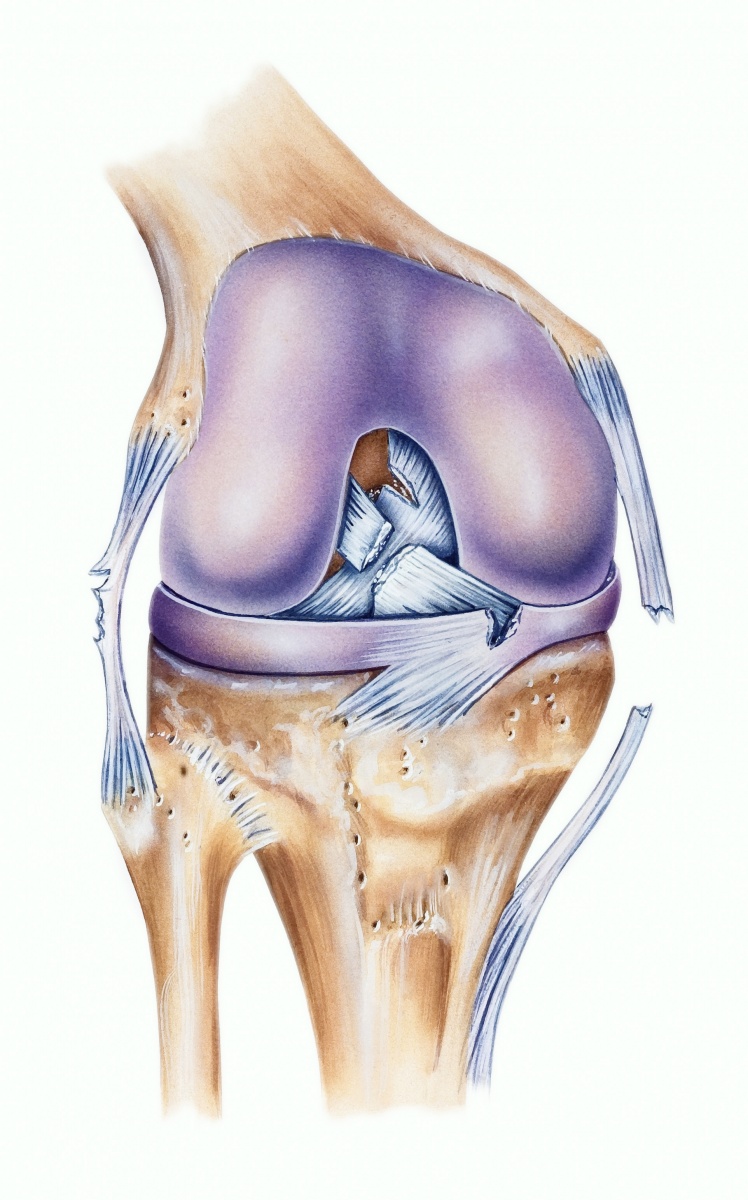

Строение коленного сустава. Повреждения мениска. Разрыв крестообразной связки. Гончаров Е.Н.

Разрыв заднего рога медиального мениска Доктор Мясников Обрезка 01